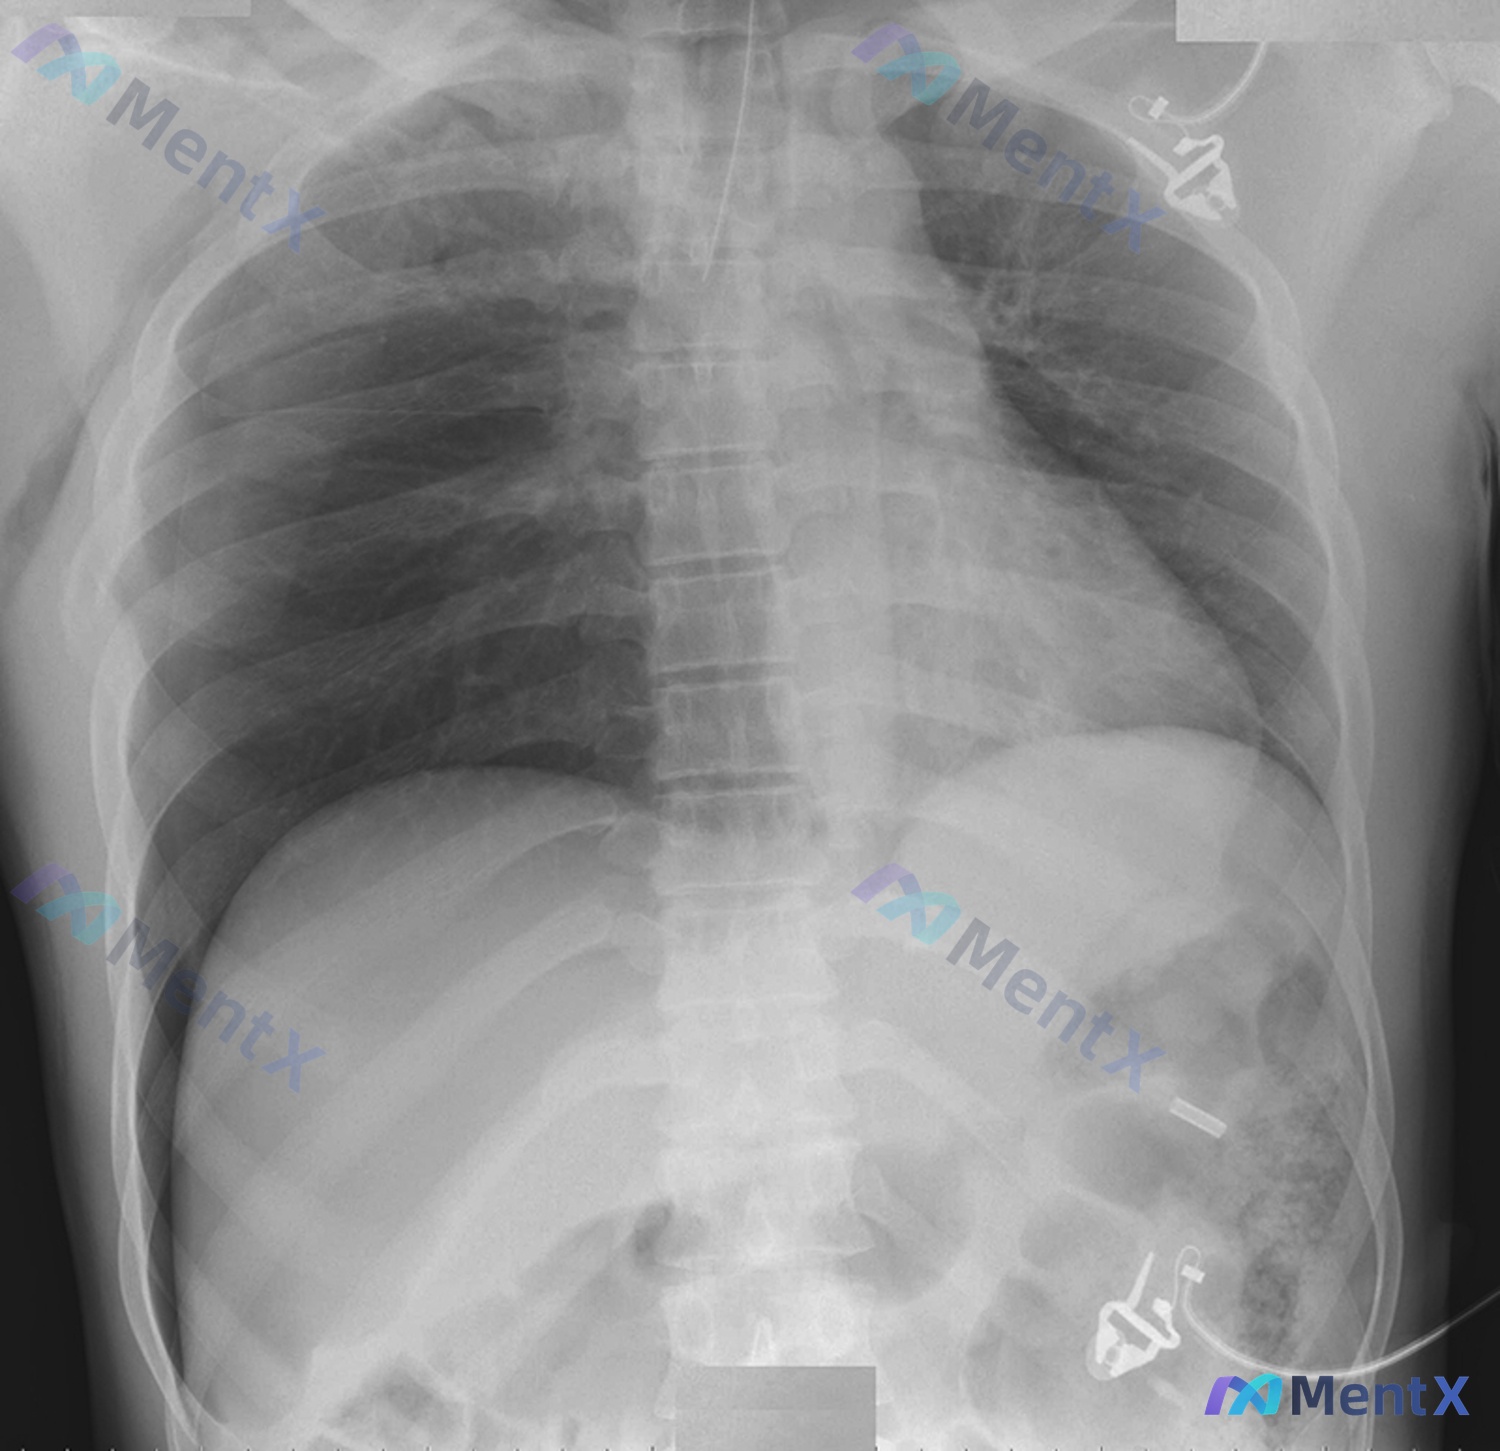

影像资料评估(胸腹部正位X线)

先看放射科的系统性读片结果:

- 技术缺陷:吸气深度欠佳(仅显示右侧第8后肋,正常应达10-11后肋),左胸/左下腹有ECG电极伪影,右侧胸廓入口有导管影。

- 主要“阴性”发现:双肺透亮度对称,未见明确气胸/实变;心影大小正常;膈下未见游离气体;肋骨/椎体未见明确骨折移位。

- 吸气深度不够:这太重要了。气胸的诊断靠的是脏层胸膜线显影,肺组织没充分膨胀起来,就算有少量气,在肺尖或肺底也可能被压扁的肺组织盖住,形成假阴性。

- 伪影遮挡:左胸电极片、右颈的导管,正好挡在肺尖这个气胸最好发的位置。

- 气胸(包括隐匿性):最常见。虽然片子没看到,但结合吸气差和伪影,X线阴性在这里完全没有排除效力。

- 膈肌破裂/隐匿性膈疝:左侧多见,因为吸气差膈肌上抬,轮廓看着“连续”可能是假象。

- 微小肋骨/椎体骨折:正位片敏感度很低,必须CT才能看。

- 主动脉损伤:虽然没看到纵隔增宽,但也不能排除,属于“宁可错查不可放过”。

结合现有信息,临床高度怀疑气胸(隐匿性可能大),绝不能因为一张“正常”胸片就放走病人。